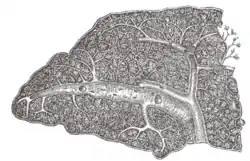

![]() Transverse section of the human spleen, showing the distribution of the splenic artery and its branches | |

The lienal artery is remarkable for its large size in proportion to the size of the organ, and also for its tortuous course. It divides into six or more branches, which enter the hilum of the spleen and ramify throughout its substance, receiving sheaths from an involution of the external fibrous tissue.

Each branch runs in the transverse axis of the organ, from within outward, diminishing in size during its transit, and giving off in its passage smaller branches, some of which pass to the anterior, others to the posterior part.

These ultimately leave the trabecular sheaths, and terminate in the proper substance of the spleen in small tufts or pencils of minute arterioles, which open into the interstices of the reticulum formed by the branched sustentacular cells.

Each of the larger branches of the artery supplies chiefly that region of the organ in which the branch ramifies, having no anastomosis with the majority of the other branches.

The arterioles, supported by the minute trabeculae, traverse the pulp in all directions in bundles (penicilli) of straight vessels.